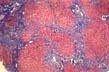

Bridging fibrosis

Central-central

Fig.69 - BRIDGING FIBROSIS: Central-central. Connects central veins with central veins. It is rare and occuring mostly in chronic passive congestion as in this case.